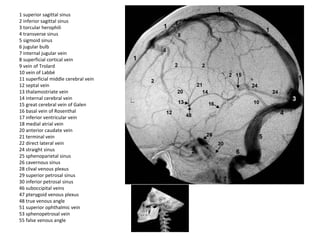

1 superior sagittal sinus

2 inferior sagittal sinus

3 torcular herophili

4 transverse sinus

5 sigmoid sinus

6 jugular bulb

7 internal jugular vein

8 superficial cortical vein

9 vein of Trolard

10 vein of Labbé

11 superficial middle cerebral vein

12 septal vein

13 thalamostriate vein

14 internal cerebral vein

15 great cerebral vein of Galen

16 basal vein of Rosenthal

17 inferior ventricular vein

18 medial atrial vein

20 anterior caudate vein

21 terminal vein

22 direct lateral vein

24 straight sinus

25 sphenoparietal sinus

26 cavernous sinus

28 clival venous plexus

29 superior petrosal sinus

30 inferior petrosal sinus

46 suboccipital veins

47 pterygoid venous plexus

48 true venous angle

51 superior ophthalmic vein

53 sphenopetrosal vein

55 false venous angle